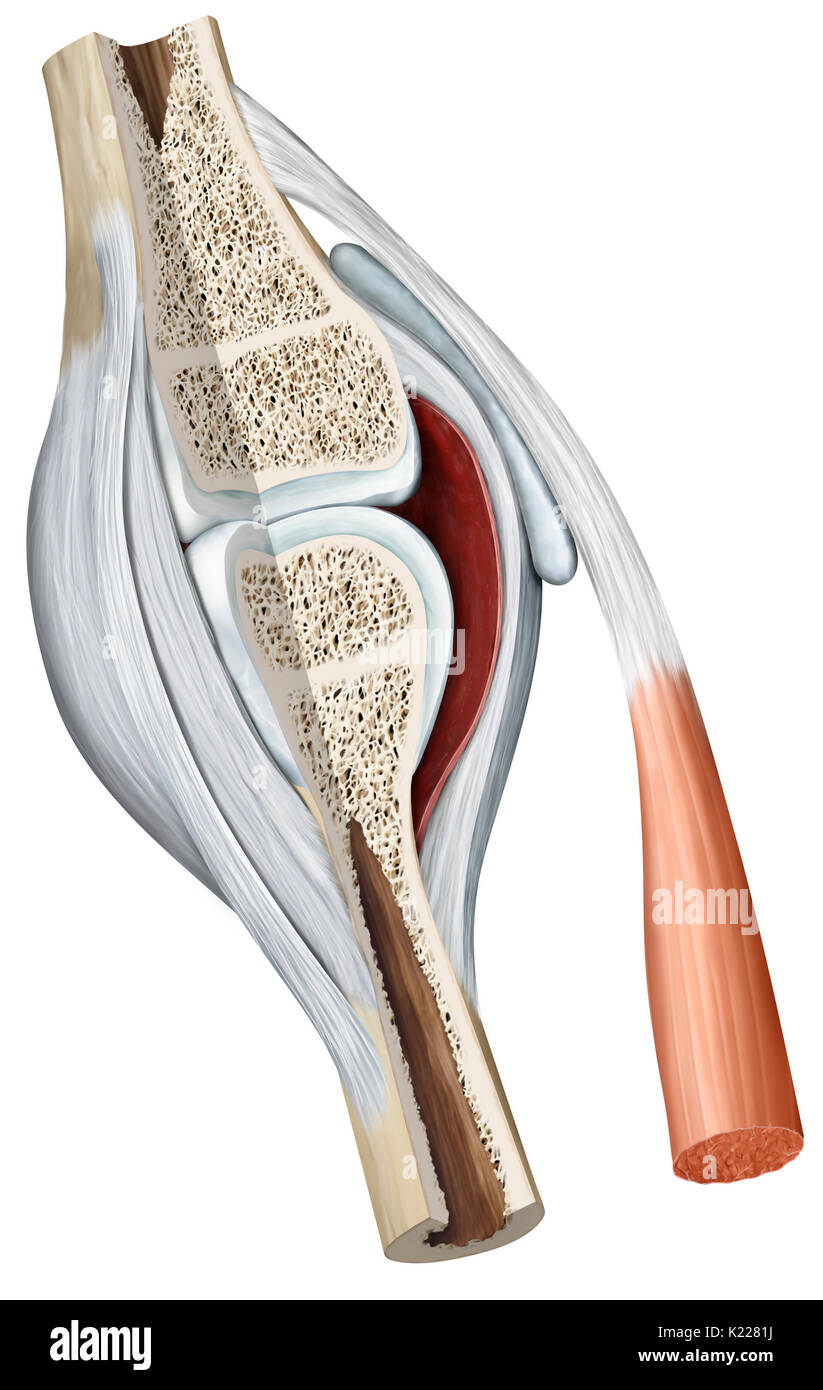

Synovial joint: joint characterized by the presence of an articular capsule filled with a viscous liquid (synovial fluid). This is the most common type of joint. Stock Photohttps://www.alamy.com/image-license-details/?v=1https://www.alamy.com/synovial-joint-joint-characterized-by-the-presence-of-an-articular-image156172846.html

Synovial joint: joint characterized by the presence of an articular capsule filled with a viscous liquid (synovial fluid). This is the most common type of joint. Stock Photohttps://www.alamy.com/image-license-details/?v=1https://www.alamy.com/synovial-joint-joint-characterized-by-the-presence-of-an-articular-image156172846.htmlRMK2281J–Synovial joint: joint characterized by the presence of an articular capsule filled with a viscous liquid (synovial fluid). This is the most common type of joint.